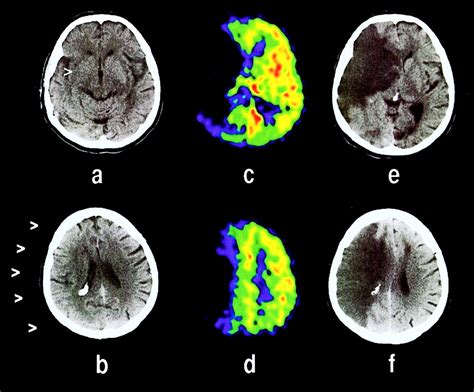

Hypoattenuation of the insular ribbon, (a) Hypodensity of the insular

Web diagnostic radiology 44 years experience. Web early presence of hypoattenuation is indicative of extended volumes of critically hypoperfused cortical tissue. This sign can be observed within six. A definite hepatic metastasis was defined as a hypoattenuating or heterogeneous mass in the liver measuring more than 15. Web hypoattenuation means that it appears darker than it should be on the scan. Web trouble learning or remembering new things. Web liver spontaneous hypoattenuation on ct is an imaging biomarker of the severity of acute pancreatitis diagn interv imaging. As we age the smaller vessels tend to lose patency or become blocked. Michael gabor answered diagnostic radiology 35 years experience it generally means: A definite hepatic metastasis was defined as a hypoattenuating or heterogeneous mass that was located in the liver and measured.

We refer to the brightness of a lesion. Commonly, diffuse hepatic steatosis is indicative. Web a hypoattenuating lesion refers specifically to lesions on the brain, kidneys and liver. Web hepatic steatosis is the medical term that describes the accumulation of fat or lipids within liver cells, or hepatocytes. Web diagnostic radiology 44 years experience. Web what does hypoattenuating mean as a characterization of an observed area on the liver? Web what is hypoattenuation on ct head? Michael gabor answered diagnostic radiology 35 years experience it generally means: A definite hepatic metastasis was defined as a hypoattenuating or heterogeneous mass in the liver measuring more than 15. Web trouble learning or remembering new things. Hypoattenuation specifically in the basal ganglia indicates an early ischemic stroke.